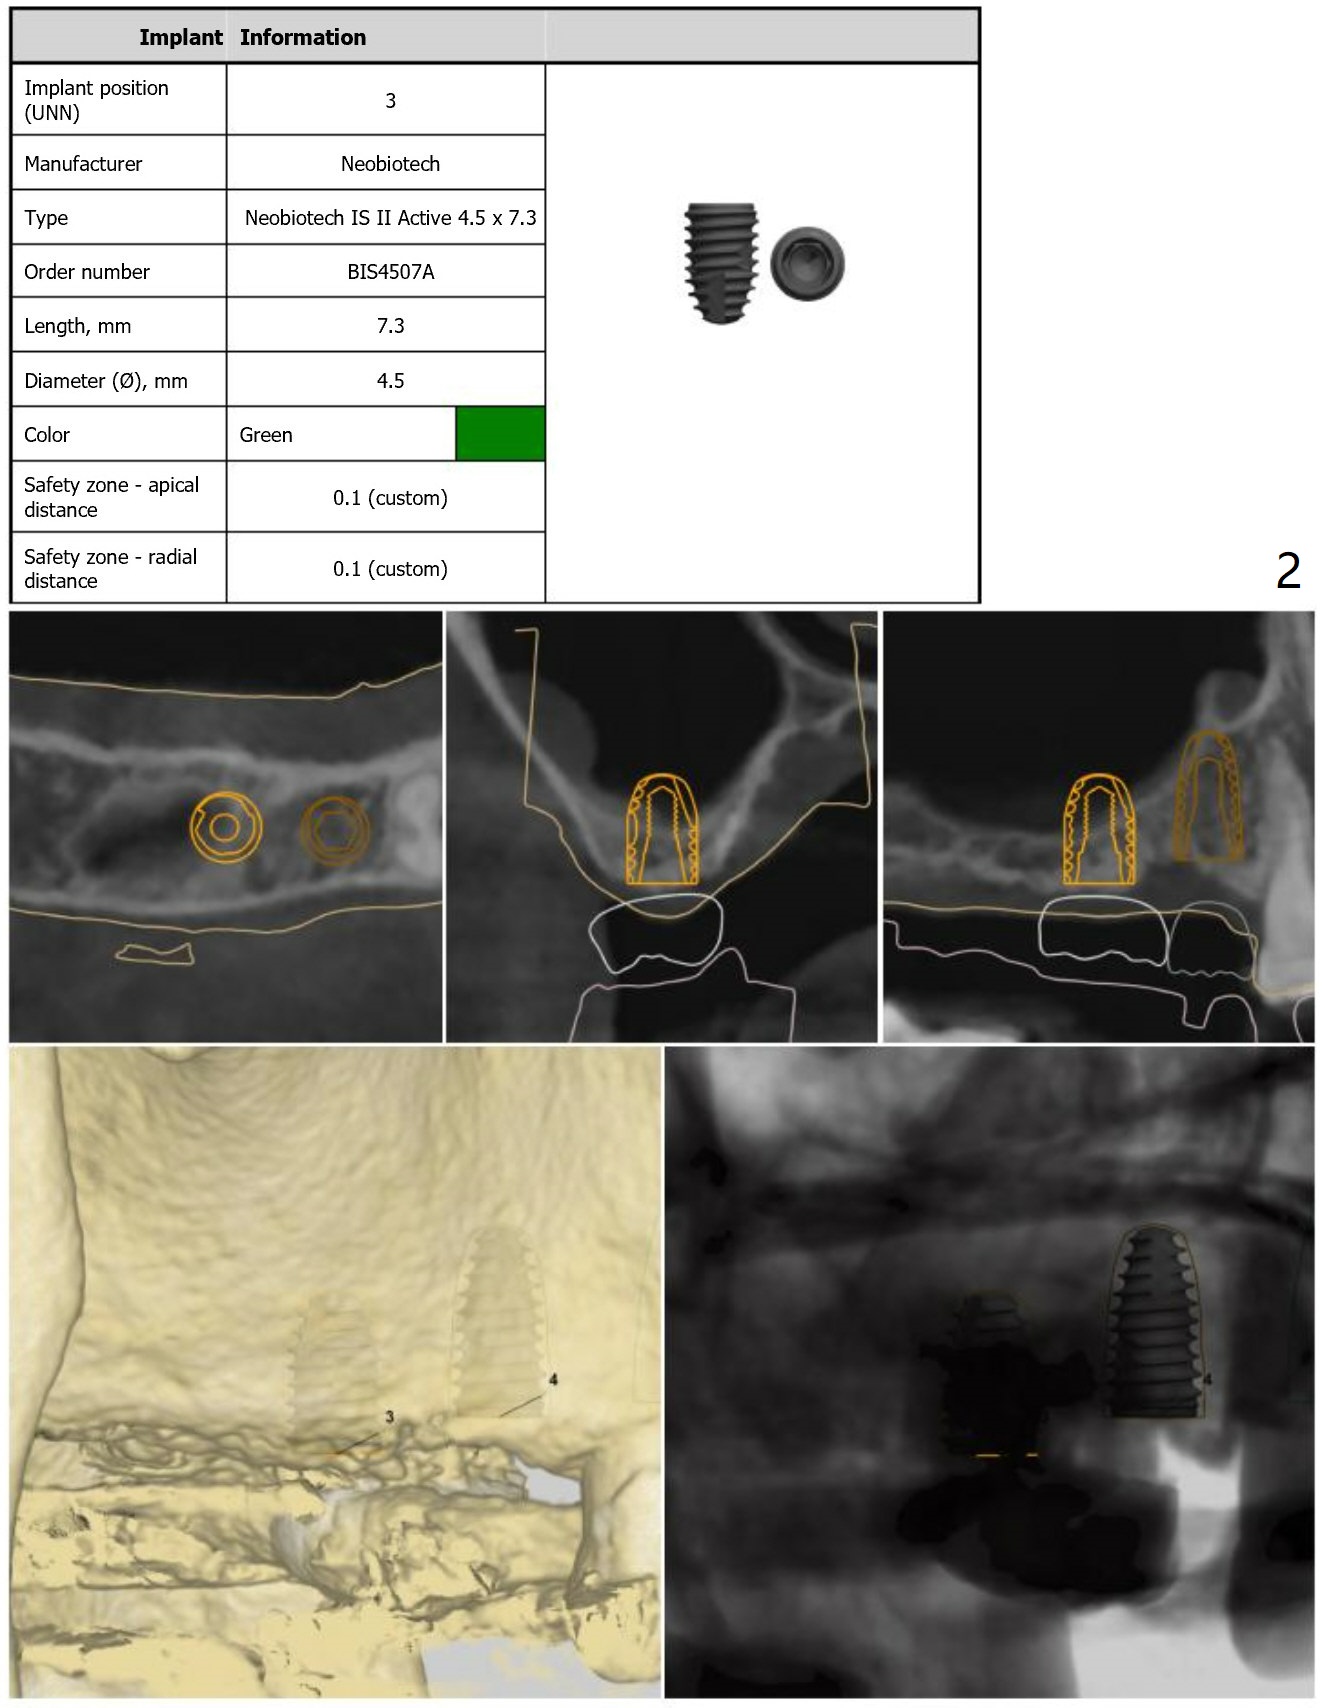

Guide for Sinus Lift

Return to Upper Arch Immediate Implant, Trajectory, No Antibiotic